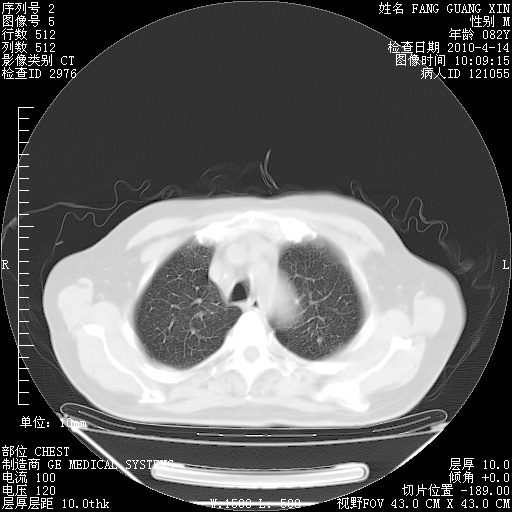

4月14日肺部CT

肺部CT平扫未见异常。